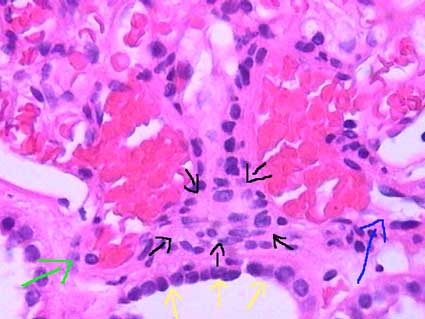

The juxtaglomerular apparatus (JGA) is formed by the terminal portion of the afferent arteriole, the first portion of the efferent arteriole, the extraglomerular mesangium (between both arterioles) and the macula densa (a plaque of very specialized and differentiated cells, in the distal straight tubule, that adheres to the vascular pole of glomerulus of the same nephron) (Figure 10, Figure 11). It has been suggested that the peripolar cells (cells located just at the transition of the parietal to the visceral epithelium) should also be included as part of JGA, nevertheless, its function is not well known (Figure 11). The JGA is innervated by the sympathetic system.

Figure 11. The juxtaglomerular apparatus is demonstrated here perfectly. The yellow arrows indicate the macula densa, see the apical nuclei. Almost in contact with macula densa cells is the extraglomerular mesangium with the Lacis or Goormaghtigh cells, indicated with the black arrows. The green arrow marks the efferent arteriole and the blue arrow the afferent arteriole. The Peripolar cells are located exactly in the angle in which parietal epithelium contacts visceral epithelium (H&E, X.400).